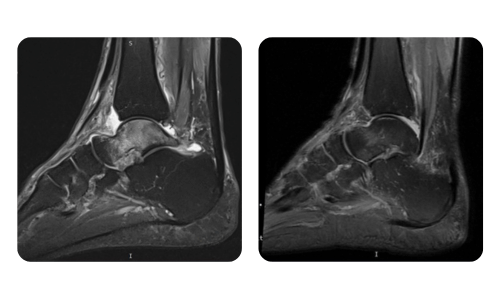

The progress of our patients, measured before and after hyperbaric therapy, reflects the efficiency and positive impact of the treatment. Discover documented results of hyperbaric therapy at Hyperbarium Oradea clinic, based on clinical evaluations and objective data that highlight significant improvements in various conditions.